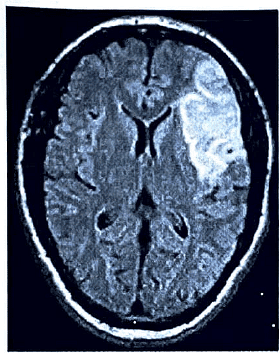

• Fluid-attenuated inversion recovery (FLAIR) is an MRI sequence utilizing inversion recovery to nullify fluid signals. For instance, in brain imaging, FLAIR can be applied to suppress cerebrospinal fluid (CSF) effects in order to enhance the visibility of periventricular hyperintense lesions, such as those associated with multiple sclerosis (MS) plaques.